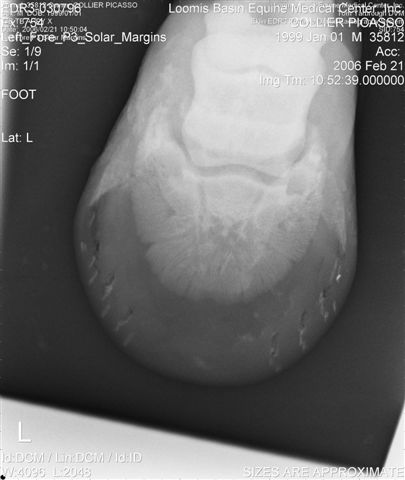

Let's label the radiographs from left to right with numbers. The abnormalities I see on the L using the photo's number as reference:

1) Odd lucency (darker) at the top/lateral margin of the coffin bone (seen in many images). It would interesting if this is also the site of the odd bruising.

2) Decrease lucency (darker) in the body of the navicular bone.

2) Remarkable cone shape areas of decrease lucency (darker) along the distal margin of the navicular bone.

3) Assymetrical flexor surface of the navicular bone.

4) There is the appearance of poor ap balance of the foot with the heels being low

4) Soles appear thin

4) Small osteophyte (bone spur) on the front margin of the pastern joint.

On the right the main problem is the appearance of the n. bone in the first image. It appears to have large irregular areas of increased lucency surrounding areas of decreased lucency. The darker areas (decreased lucency) may be artifacts or represent thinning of cortical bone.

Unless there is something I am missing in the images the extensor process appears to have healed well on the L. The significance of each of these lesions will depend on clinical findings Ann and confirmation that these are actual lesions and not artifacts created by positioning or the foot preparation for radiography. You should note I am not a radiologist and that viewing images in this manner is not as revealing as viewing the radiographs first hand.